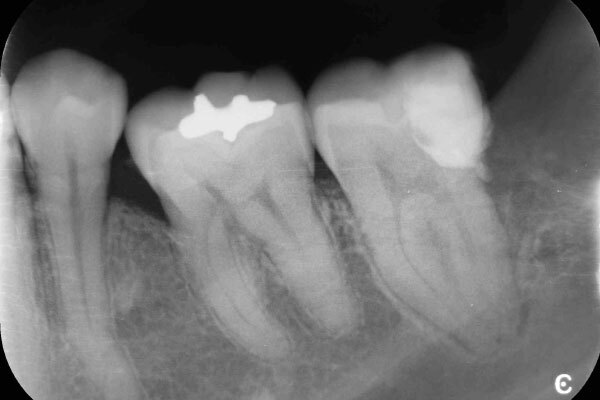

術前のデンタルX線写真と口腔内写真です。右上の前から6番目の歯(#26)です。

術直後のデンタルX線写真です。

術後1ヵ月のデンタルX線写真です。

自覚症状はなく、レントゲン写真でも異常所見は認めません。